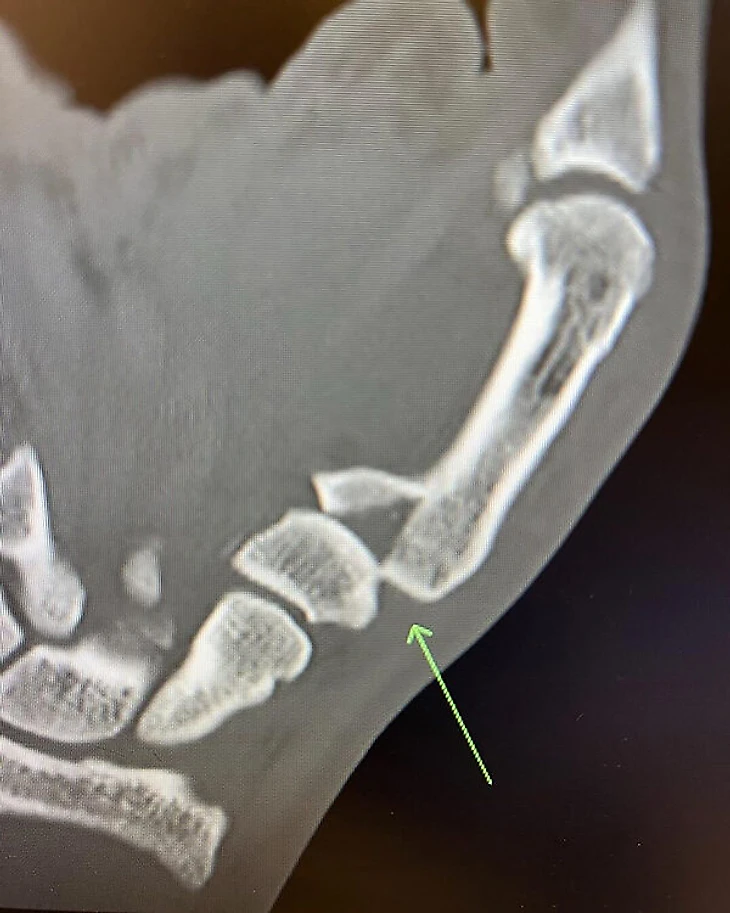

После победы он опубликовал снимок перелома: «Сломал большой палец во втором раунде, но это нас не останавливает! Сегодня у меня операция. Я пропущу 12 недель». Уже следующим соперником стал Махачев, но до их февральской встречи прошло больше полугода.

В июле-2022 Волкановски уверенно разобрал Макса Холлоуэя в титульном поединке (все судьи отдали 50-45). При этом дрался с переломом: «Я сломал руку во втором раунде. Это немного усложнило борьбу, но я все еще мог наносить джеб. Это не помешало мне делать то, что я хотел. Несмотря на то, что это было больно, оно того стоило».